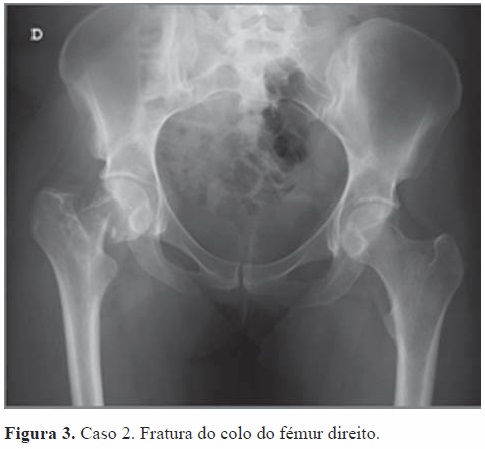

Dois meses após o nascimento do segundo filho sofreu queda de bicicleta de baixa energia (encontrava-se parada, desequilibrou-se e caiu). Inicialmente foi observada no SU de outra instituição hospitalar, após o que teve alta com indicação de repouso e analgesia. Ao fim de dois dias deu entrada no nosso SU, por persistência e agravamento das queixas álgicas, com incapacidade para a marcha. Realizou estudo radiológico da bacia que revelou fratura do colo do fémur, tipo III de Garden[3] (Figura 3).

A doente foi submetida a redução fechada da fratura e osteossíntese com parafusos canulados (Figura 4). Decorridos seis meses após a cirurgia (Figura 5), deambula com apoio de canadianas, tem rigidez á mobilização da anca operada, pelo que se encontra em programa de reabilitação fisiátrica.